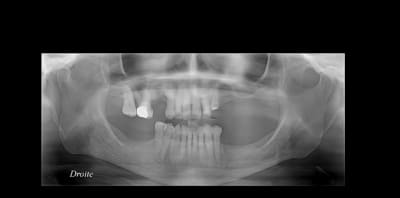

salut a tous. une patiente d'un certain age ce presente pour un traitement prothetique sans avoir recours a une solution implantaire.

J'ai decidé de faire deux CCM avec attachement de chaque coté au niveau mandibulaire auxquels s'attachera un stellite.

Au niveau maxillaire apres extraction de la 16 on va realiser deux CCM sur la 13 et la 17 qui seront reliés par une barre qui servira d'attachement.

Mais le probleme se pose du coté gche: d'une part la 22 est mobile, versée et avec une proximité radiculaire compromettante pour la 21 qui déja commence a souffrir du coté distal.

Est il meilleur de conserver la 21 et de réaliser un bridge 21-22-23 ou bien extraire 21 et 22 et le bridge sera de 11 jusqu'a la 23 (bien evidement avec attachement + stellite sup )

a propos de la 16: la radio n'est pas tres claire mais cliniquement il y a une atteinte de furcation et perte d'attache assez importante au niveau de la racine palatine.

La 23 a ete retraitée par moi meme et la peche a tendance a disparaitre sinon resection apicale pour conserver cette racine assez longue coute que coute.

La patiente est assez exigente esthétiquement et ne veut pas de crochets visibles d'ou la necessité de "mutiler" des dents saines et je doute que la patiente puisse supporter une PAP résine.